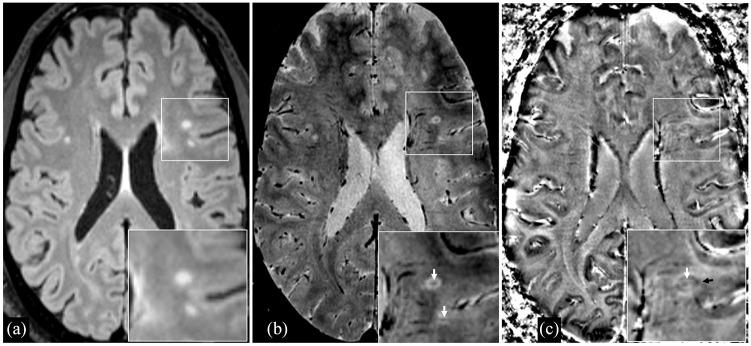

The central vein sign (CVS) and "paramagnetic rim lesions" (PRL) are emerging imaging biomarkers in multiple sclerosis (MS) reflecting perivenular demyelination and chronic, smoldering inflammation. The objective of this study was to assess relationships between cognitive impairment (CI) and the CVS and PRL in radiologically isolated syndrome (RIS).

Twenty-seven adults with RIS underwent 3.0 T MRI of the brain and cervical spinal cord (SC) and cognitive assessment using the minimal assessment of cognitive function in MS battery. The CVS and PRL were assessed in white-matter lesions (WMLs) on T2*-weighted segmented echo-planar magnitude and phase images. Multivariable linear regression evaluated relationships between CI and MRI measures.

27 名成人 RIS 患者接受了 3.0T 脑部和颈脊髓(SC)磁共振成像(MRI)以及使用 MS 最小认知功能评估(MACFIMS)进行认知评估。在 T2*-加权分段回波平面幅度和相位图像上的白质病变(WML)中评估 CVS 和 PRL。多变量线性回归评估 CI 与 MRI 测量之间的关系。